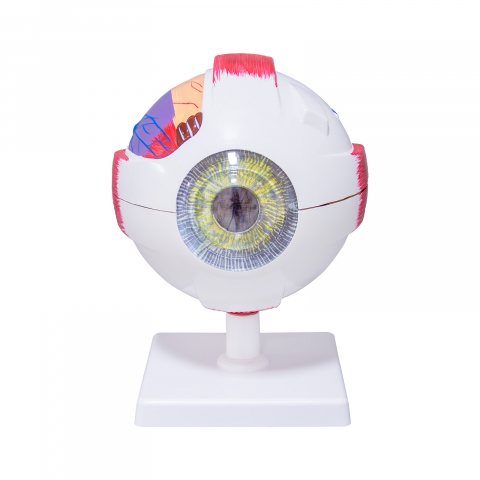

Modelul este conceput din material plastic PVC și este frumos colorat.

Acest model este conceput ca ajutor vizual pentru predarea cursurilor de anatomie umană și igienă. Este folosit pentru a demonstra structura dintelui, la studiul sistemului digestiv în gimnaziu, liceu și școli postliceale medicale.

Acest model are înălțimea de 23-26 cm, prezintă 3 rădăcini, o secțiune longitudinală prin care se poate observa structura interioara a dintelui, este conceput din material plastic PVC și este frumos colorat.